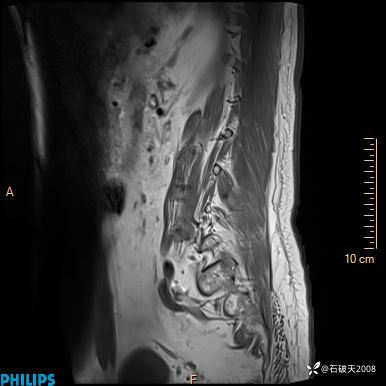

2023年3月份MRI影像

DWI